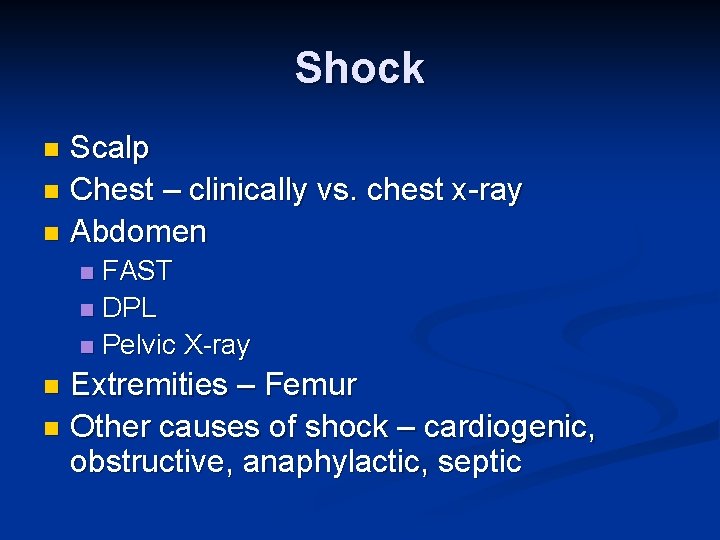

Shock Scalp n Chest – clinically vs. chest x-ray n Abdomen n FAST n DPL n Pelvic X-ray n Extremities – Femur n Other causes of shock – cardiogenic, obstructive, anaphylactic, septic n